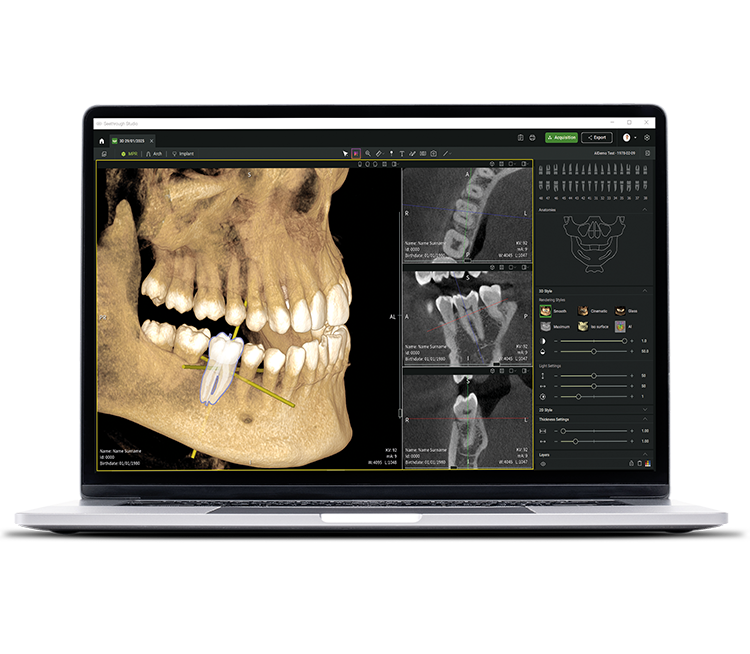

Yeni seviyeyi gör. Geleceği gör.

Gelişmiş donanım teknolojilerinin yanı sıra, devrim niteliğindeki Seethrough Studio yazılımı, W&H görüntüleme portföyünün yüksek standardının belirleyici bir faktörüdür. Kullanışlı özellikleri ve gelişmiş yapay zeka özellikleriyle Seethrough Studio, görüntüleme kalitesini ve dijital diş hekimliği iş akışlarını yeni bir düzeye taşıyan hepsi bir arada bir çözümdür.

Entegre implant planlama aracı

Seethrough Studio, olağanüstü görüntü kalitesi ve sezgisel kullanımının yanı sıra, tedavinin kolay görselleştirilmesi ve hazırlanması için standart entegre implant planlama aracı gibi birçok kullanışlı özellik sunar.

Seethrough Studio, görüntü iyileştirme için 3D hacim hizalama, diş segmentasyonu, kemer çizgisi oluşturma, otomatik sinir izleme ve patoloji tespiti için yararlı destek dahil olmak üzere çeşitli AI araçlarını kullanır.